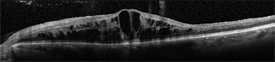

Swelling of the center of the retina, called macular edema is common, and to detect this and measure the amount of swelling, an optical coherence tomography (OCT) image is often obtained (Figure 2). To help distinguish CRVO from conditions that may mimic it, and to assess closure of small blood vessels, or to search for or confirm growth of new abnormal vessels, fluorescein angiography (FA) imaging may be performed.